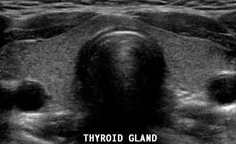

갑상선이란?

먼저 갑상선은 사람의 신체기관 중 하나로 목 중앙에 위치해있습니다.

후두와 기관에 붙어있는 내분비샘으로 한자 甲의 모양을 닮아서 갑상선이라는 이름이 붙여져있습니다.

모양은 나비를 연상시키고 있고 무게는 12~20g정도 입니다.